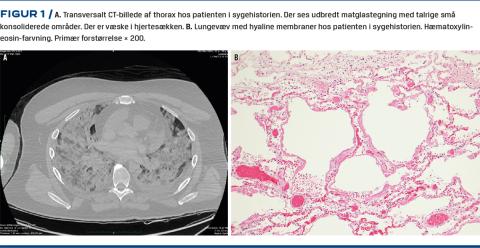

PMCT viste udbredt matglastegning med talrige små konsoliderede områder (Figur 1A). De mediastinale lymfeknuder var ikke forstørrede.

Den mikroskopiske undersøgelse af ni vævsprøver fra centrale og perifere dele af alle lungelapper viste udbredt forekomst af diffus, alveolær skade med hyaline membraner og varierende mængde væske samt pleomorfe og degenererede celler i alveolerne (Figur 1B). Der var sparsom interstitiel inflammation domineret af lymfocytter. Der var desuden mindre områder med bronkopneumoni med forekomst af fibrin og neutrofile granulocytter i alveolerne. Forandringerne var akutte uden tegn på opheling eller organisering. Der var ingen forudbestående lungesygdom. Der var et sparsomt betændelsesinfiltrat med få lymfocytter i lamina mucosa af de øvre luftveje (larynx og trachea). Tonsillerne var upåfaldende. Der var ikke tegn på inflammation i andre organer, ej heller myokarditis. Der var svær fedtlever.

PMCT viste omfattende lungeforandringer, og CT kan på den måde give et forhåndsvarsel om muligheden for COVID-19. Zhu et al [3] har i en metaanalyse af CT-fund hos 4.121 patienter konstateret, at lungeforandringerne hyppigst var bilaterale og især omfattede matglastegning og pletvis konsolidering, altså svarende til fundene hos patienten i sygehistorien.